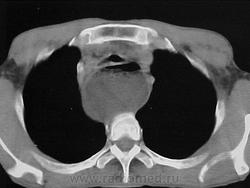

На протяжении второй стадии паразиты концентрируются, в основном, в сердце или мускулатуре пищеварительного тракта. До 30% пациентов страдает от нарушений сердечной деятельности и до 10% – от изменений в органах пищеварения (характерна гипертрофия пищевода или толстой кишки), нервной системе или целом ряде органов. В последующие годы инфекция может приводить к внезапной смерти или сердечной недостаточности, вызываемой прогрессивным разрушением сердечной мышцы.